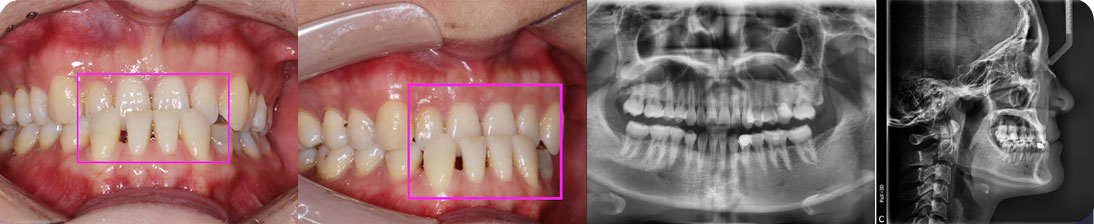

- 【診斷】

先天缺少下切牙2顆

上前牙錯(cuò)位于下前牙后側(cè),前牙無(wú)咬合功能,上牙槽及上唇后縮

打造醫(yī)生:德倫口腔正畸中心鄧毅醫(yī)生

- 【治療方案】

調(diào)整弓形及配合Ⅲ類牽引,實(shí)現(xiàn)頜跳躍

矯治前后對(duì)比

牙列整平排齊,前牙內(nèi)收;覆蓋、覆合正常;尖牙和磨牙達(dá)到中性關(guān)系;上下中線對(duì)齊;下頜后縮改善